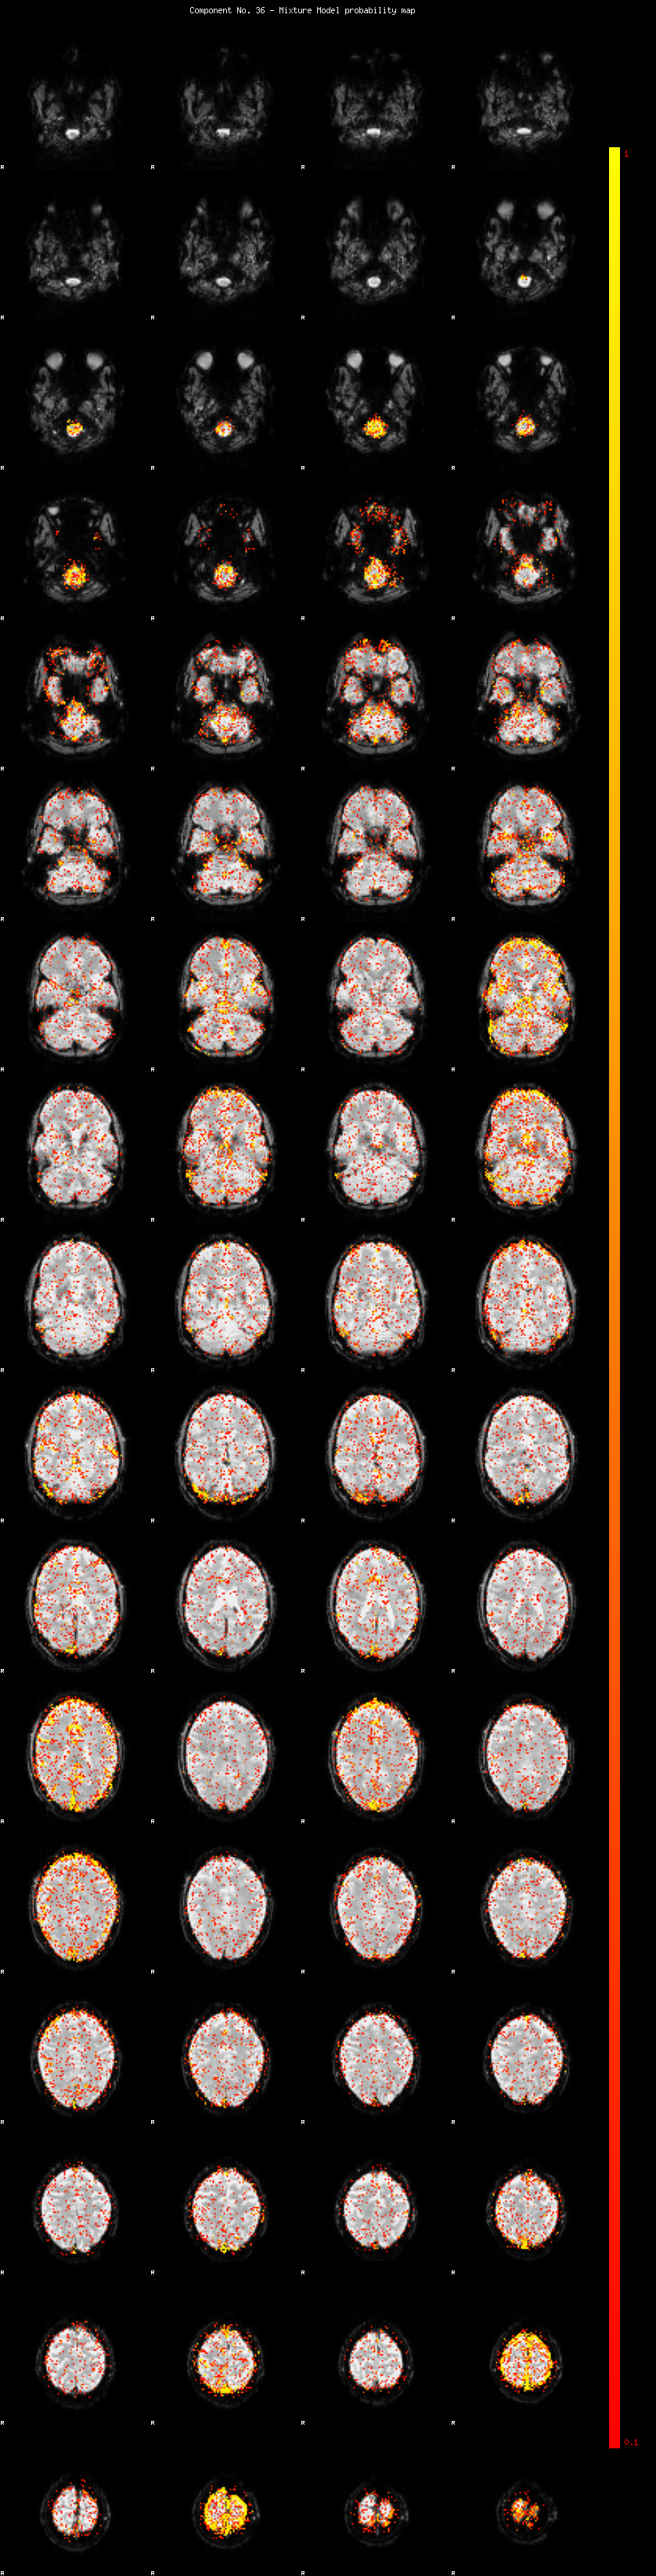

IC_36 Mixture Model fit

Means : 0.000000 2.735653 -2.466137

Vars : 1.000000 2.875196 1.969567

Prop. : 0.925363 0.039922 0.034715